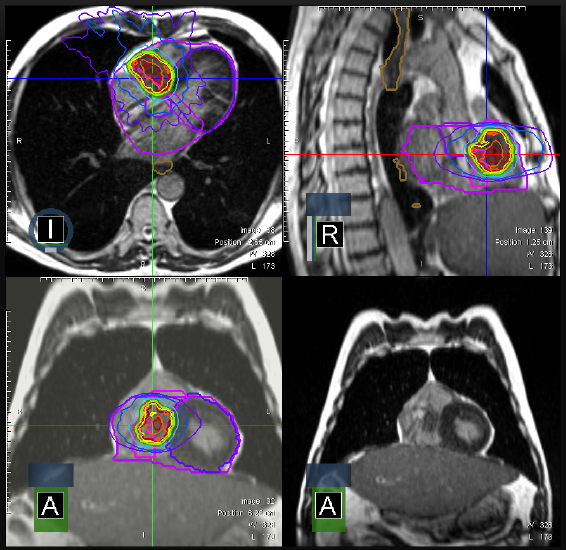

Aufnahmen eines Herztumors

„So können wir live und direkt verfolgen, ob und wie sich ein Tumor und das umgebende gesunde Gewebe durch die Therapie verändern“, sagt Privat-Dozentin Dr. Stefanie Corradini, leitende Oberärztin an der Klinik und Poliklinik für Strahlentherapie und Radioonkologie. „Damit können wir die gesamte Therapie sehr präzise gestalten und an die sich ändernden Verhältnisse im Krebsgewebe anpassen.“ Und zwar Tag für Tag. Denn die jeweils nächste Sitzung der Therapie wird immer neu von einem mehrköpfigen Team aus Ärztinnen und Ärzten, Medizinisch-Technischen Angestellten und Physikerinnen und Physikern für die aktuellen Verhältnisse im Gewebe berechnet.

Internationale SHARP-Studie startet

Dabei ermöglicht das High-Tech-Verfahren sogar die Behandlung von bösartigen Herztumoren. Diese Tumore sind zwar extrem selten. Da sie nicht operiert werden können, haben die Patienten bisher keine Therapieoption und geringe Überlebenschancen. „Wir können die Betroffenen mit hohen Dosen bestrahlen und ihre Tumoren in Schach halten“, sagt Stefanie Corradini. Das heißt: Die Krebsherde wachsen nicht weiter oder sie schrumpfen sogar. Auch Herzmetastasen lassen sich mit dem MR Linac behandeln. Inwieweit das Verfahren das Überleben der Patientinnen und Patienten langfristig verlängert, wollen die Experten des LMU Klinikums jetzt gemeinsam mit drei weiteren Krankenhäusern in einer großen internationalen Studie ermitteln. (SHARP trial - Stereotactic Heart Ablative RadiotheraPy - Prospektive Beobachtungsstudie zur MR-gesteuerten stereotaktischen ablativen Strahlentherapie von inoperablen primären oder rezidivierenden malignen Herzsarkomen oder Herzmetastasen).